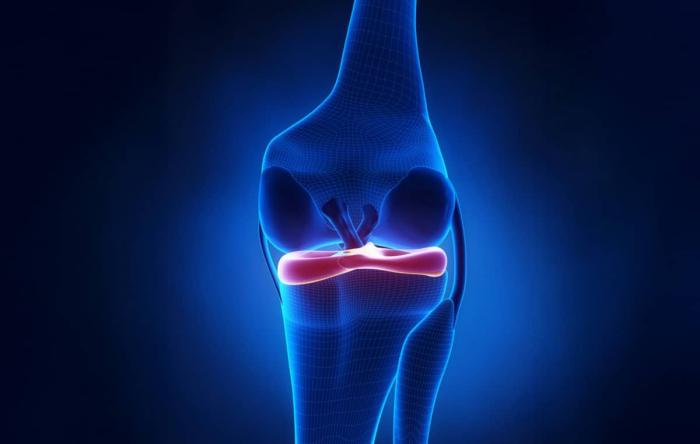

How Do You Know If Your ACL Surgery Failed?

ACL surgery is performed more than 100,000 times...